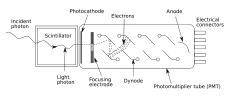

Гамма-камера

Гамма-камера — сцинтилляционная камера, регистрирующая гамма-излучение. В сцинтилляторе гамма-камеры поглощённые или рассеянные гамма-кванты преобразуются в фотоны видимого излучения, причём количество излученных фотонов пропорционально поглощённой в сцинтилляторе энергии гамма-кванта. Фотоумножители преобразуют световую вспышку в сцинтилляторе в импульс тока, который регистрируется спектрометрической аппаратурой. Амплитуда импульса пропорциональна поглощённой в сцинтилляторе энергии гамма-кванта, поэтому возможно отделение вспышек от гамма-квантов с энергией, характерной для используемого маркера, от фона. Применение сборки фотоумножителей позволяет осуществить восстановление координат вспышки и, таким образом, измерить пространственное распределение маркера в теле пациента.

Сцинтилляционная гамма-камера — медицинский прибор для радиоизотопной диагностики. Представляет собой многоканальный коллиматор; на выходе каждого из каналов установлены ФЭУ (фотоэлектронные умножители - высокочувствительные детекторы фотонов), сигналы которых обрабатывают на компьютере. После введения в организм препарата, меченного радиоактивными изотопами, с помощью гамма-камеры можно получить на экране картину распределения препарата в исследуемом органе, а также наблюдать в динамике процесс его выведения.

Гамма-камера состоит из детектора (большого сцинтилляционного кристалла, обычно из NaJ(Tl)[уточнить]), световода, набора ФЭУ, сменных свинцовых многоканальных коллиматоров и блока аналоговых электронных устройств, обеспечивающих определение координат и амплитуд сигналов, компьютера и консоли оператора.

Система для диагностики всего тела требует наличия подвижного детектора, который проходит вдоль тела пациента, либо подвижного стола, который движется под неподвижным детектором. Во избежание погрешностей, привносимых излучением от посторонних источников, детектор помещают в защитный кожух, выполненный из свинца или его сплавов. Пространство, с которого на детектор поступает излучение, ограничивается и формируется сменными диафрагмами (коллиматорами) из свинца, которые имеют разную форму в зависимости от типа исследования. Толщина свинцовой защиты зависит от применяемых изотопов. Излучение должно ослабляться защитой в 1000 раз[уточнить]. Для излучения с энергией 140 кэВ достаточно свинцовой защиты толщиной 10 мм, а для энергии 500 кэВ необходимо 50 мм.